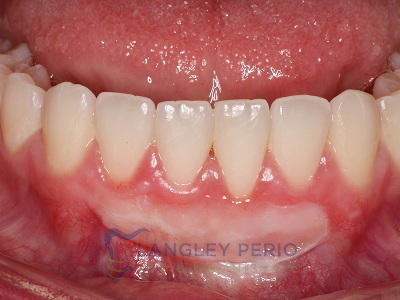

Case 1

Connective tissue grafting was performed to correct gingival clefting caused by over-aggressive toothbrushing